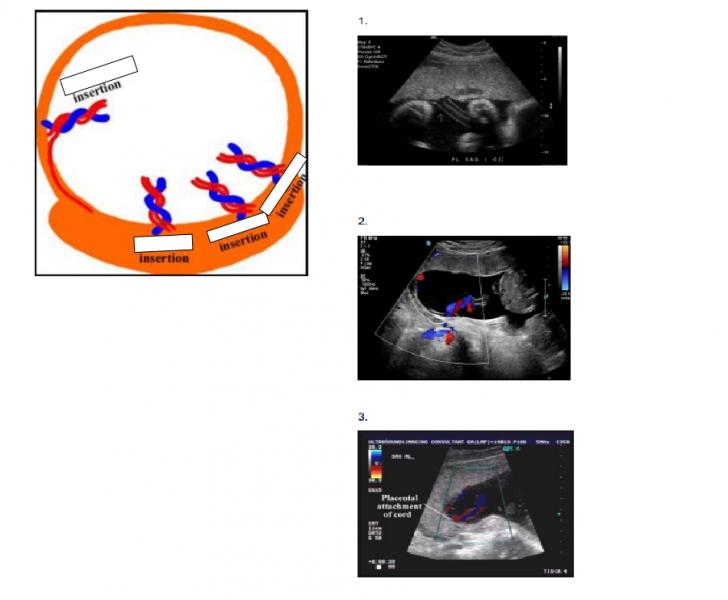

Placental Insertion

by Heather Shirley

1 velamentous insertion (diagram) 2 Normal insertion (diagram) 3 Eccentric insertion (diagram) 4 Marginal insertion (diagram) 5 Central insertion (ultrasound) 6 velamentous insertion (ultrasound) 7 Marginal (battledore) insertion ultrasound